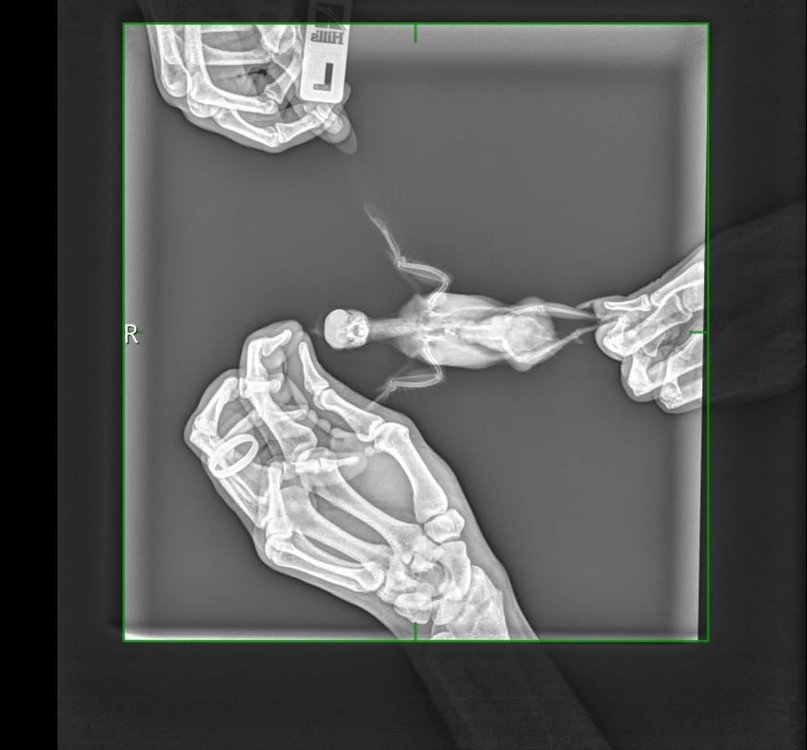

Снижение общей прозрачности лёгочных полей. Умеренное увеличение тени печени. Повышенная рентгенологическая контрастность почек.

попугай.JPG

попугай1.JPG

Печень действительно выглядит увеличенной...